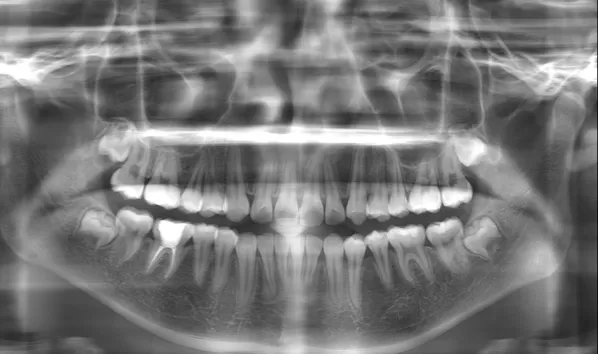

X-rays before treatment

[Panoramic Radiography/Lateral Cephalogram]